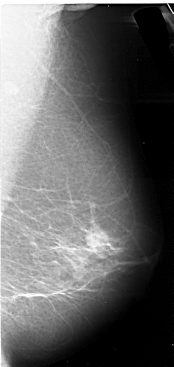

A_1107_1.LEFT_MLO

LEFT_MLO LINES 5506 PIXELS_PER_LINE 2866 BITS_PER_PIXEL 16 RESOLUTION 42 OVERLAY

FILE: A_1107_1.LEFT_MLO.OVERLAY

TOTAL_ABNORMALITIES 1

ABNORMALITY 1

LESION_TYPE CALCIFICATION TYPE FINE_LINEAR_BRANCHING DISTRIBUTION LINEAR

ASSESSMENT 4

SUBTLETY 2

PATHOLOGY MALIGNANT